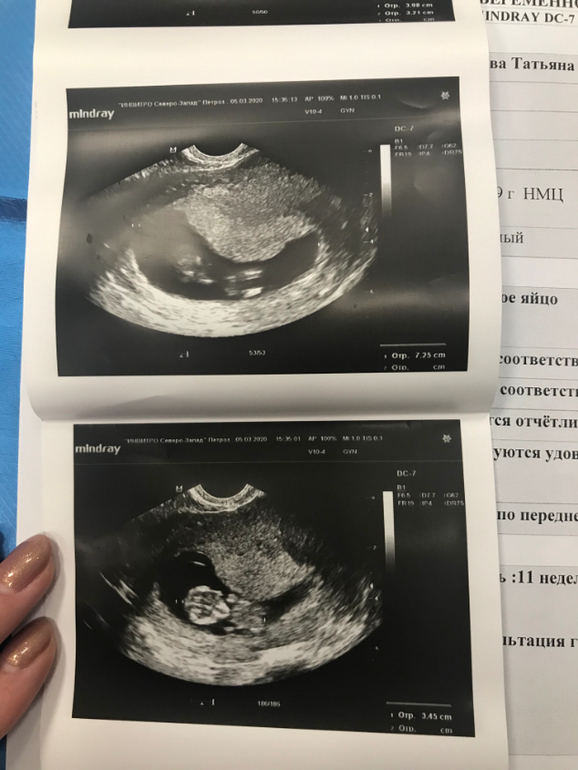

11 неделя - ПЯ кривое

Не всё гладко. к сожалению. Появилась миома, но Г сказала ничего страшного, будем наблюдать. И бесконечный гипертонус, который видимо приводит плодное яйцо в жуткое состояние (на картинке). Я смотрю на фото узи других и вижу, какие у них красивые овальные и круглые домики, а у меня вечно все через ж... Сначала писали ПЯ неправильной формы, потом деформированное, короче какое-то оно странное. Видела вчера на узи как малышу тесно в таком(( Сказали, что пя все равно тоже растет и должно быть всё нормально.

А это в 11